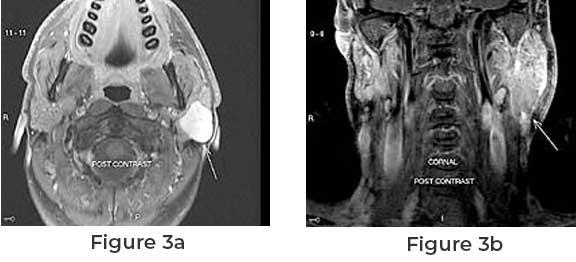

in the affected area. Diagnosis is often confirmed through imaging techniques

like ultrasound or MRI, followed by a biopsy to assess the tumor’s nature and

rule out malignancy.